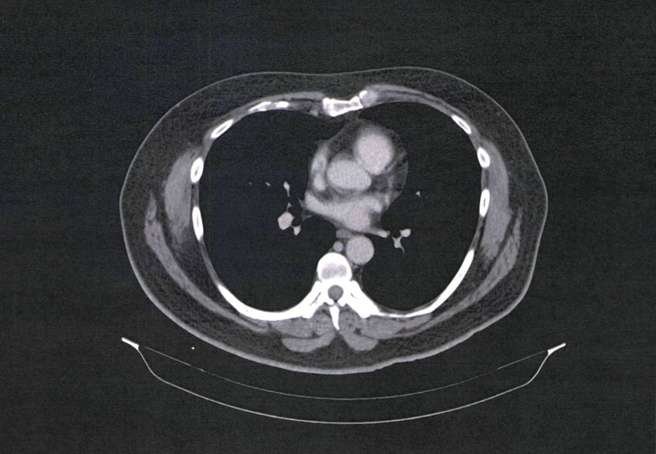

De beelden betreffen onder andere röntgen-, ct- en mri-afbeeldingen van scans. Het probleem ligt bij de beveiliging van pacs, oftewel picture archiving and communication systems. Scanners sturen de beelden naar deze pacs voor archivering, zodat medische instanties ze daarna kunnen opvragen. De verbinding tussen deze servers is gebaseerd op de Dicom-standaard, die zijn oorsprong in de jaren tachtig van de vorige eeuw heeft. Bij de implementatie van de pacs en Dicom worden regelmatig niet de juiste beveiligingsvoorschriften in acht genomen, waardoor de systemen direct op internet zijn aangesloten, zonder maatregelen als firewalls en vpn's.